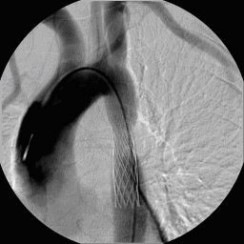

Erfolgreiche Implantation eines transjugulären intrahepatischen portosystemischen Shunts (TIPSS) bei Leberzirrhose und refraktärem Aszites. Darstellung der Lebervenen

(Bild 2 von 4)

Erfolgreiche Implantation eines transjugulären intrahepatischen portosystemischen Shunts (TIPSS) bei Leberzirrhose und refraktärem Aszites. Transhepatische Punktion der Pfortader unter sonographischer Kontrolle

(Bild 3 von 4)

Erfolgreiche Implantation eines transjugulären intrahepatischen portosystemischen Shunts (TIPSS) bei Leberzirrhose und refraktärem Aszites. Implantation eines Stentgrafts

(Bild 4 von 4)